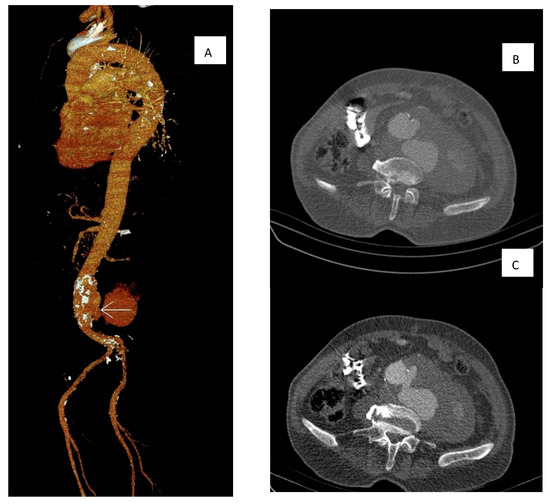

Multidetector computer tomography angiography (MDCTA) was performed, showing a ruptured distal abdominal aorta with left-sided retroperitoneal leakage, with no evidence of aorto-caval fistula (Figure 1). Empirical antibiotic therapy with ceftriaxone was initiated. The patient underwent an emergency vascular repair. The retroperitoneal space was reached through a median laparotomy. The aneurysm was clamped under the renal arteries. The aneurysmal sack was opened with a longitudinal incision. After the removal of the mural thrombus, an aorto-caval fistula was verified, and it was sutured with prolene 4–0. Aneurysm resection and silver-knitted dacron tube graft interposition with end-to-end anastomoses were performed. Intraoperative blood loss was approximately 0.5 L. Total perioperative blood transfusion was approximately 1.2 L red blood cell transfusion and 910 mL plasma transfusion.

Figure 1. Multidetector Computer tomography angiography was performed showing a ruptured distal abdominal aorta. (A) Reconstruction of the MDCTA showing the jet (arrow) and retroperitoneal hematoma. (B) Jet from the ruptured aneurysm. (C) Maximum hematoma size.